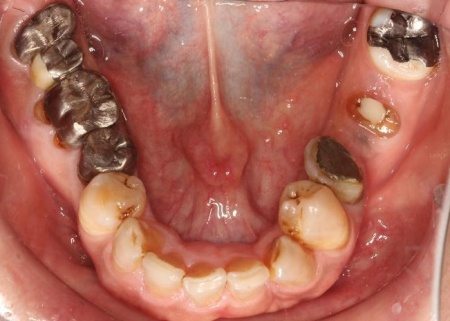

拝見したところ、もともと左上の歯と左下前歯が欠損しているうえ、奥歯の欠損も進んでいたため、噛み合わせが低くなっていました。

奥歯が噛み合わない状態になったことで、上前歯が前方に押し出され、出っ歯のようになっています。

また、下の歯は歯根だけが残る「残根」もあり、全体的に噛み合わせが不安定です。

さらに食いしばりの習慣があることから、残っている歯や顎関節に過度な負荷がかかっていると考えられます。